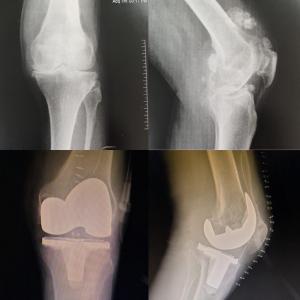

Orthopedic

Revision Knee & Hip Replacement

Complex Joint Replacement Surgery